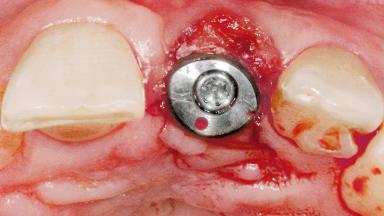

Late Flapless Placement of an Implant in a Maxillary Left Central Incisor Site

| Abutment Type | Standard |

| Prosthesis Type | FDP |

| Retention | Cemented, with prosthesis margin < 3mm submucosal Cemented, with prosthesis margin < 3mm submucosal |

| Provisional Implant-Supported Prosthesis | Prosthodontic margin < 3 mm apical to mucosal margin Prosthodontic margin < 3 mm apical to mucosal margin |